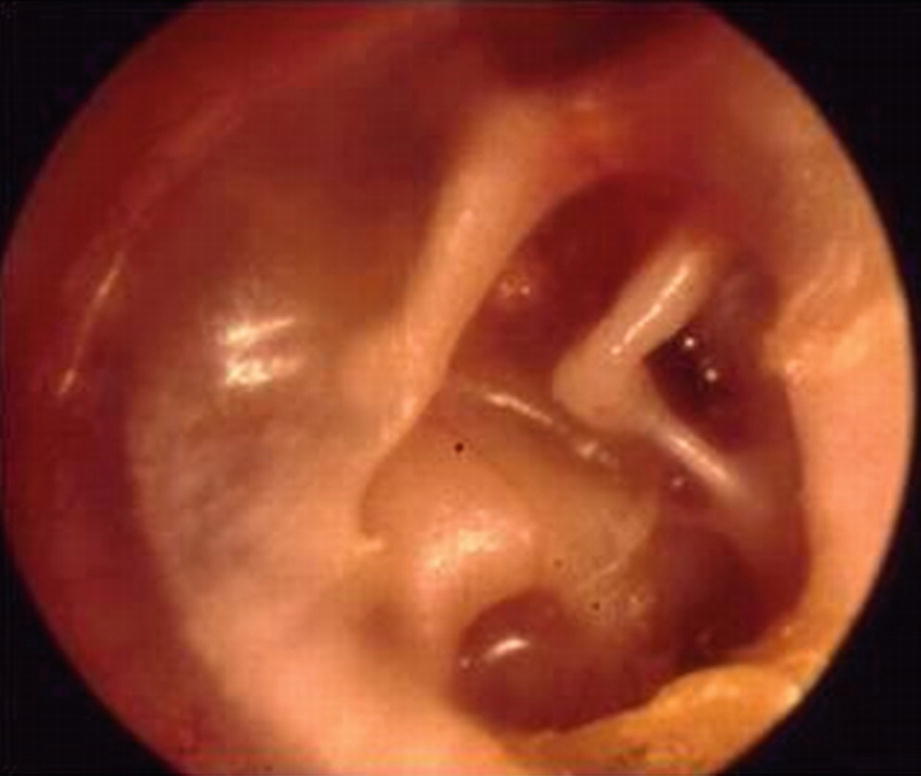

Tympanic Membrane Retraction Classification Note Sade Grade 3 Retracted Tympanic Membrane Touching Promontory Toss Grade 5 Membrane Sade Disorders